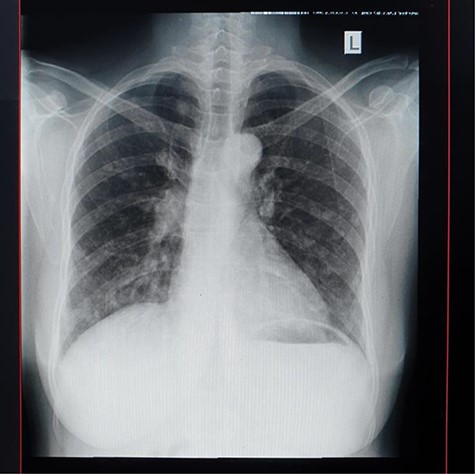

Plain abdominal X-ray (supine) showed grossly dilated large bowels (Fig. 1), and a chest X-ray showed a right-sided pneumothorax, which was managed by a thoracostomy tube (Fig. 2).

Chest X-ray showing right-sided pneumothorax with thoracostomy tube.